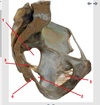

2

3

4

5

Perfectly

10

Q

9

A

adductor magnus

How well did you know this?

1

Not at all

11